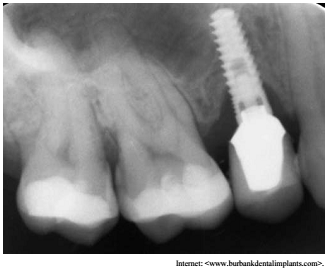

Um paciente que havia recebido implante unitário colocado no lugar do dente 15, não compareceu às visitas de manutenção e retornou dois anos depois, com a condição apresentada na imagem precedente. O tecido mole peri-implantar apresentava sinais clínicos de inflamação, com supuração e sangramento à sondagem.

Com base na situação hipotética e na figura apresentadas, julgue o item que se segue.

O controle microbiano da superfície exposta do implante é essencial para o sucesso de terapia, de modo que tratamentos como aplicação de laser, fototerapia, antimicrobianos tópicos e aeropolidores podem ser associados à terapia mecânica.